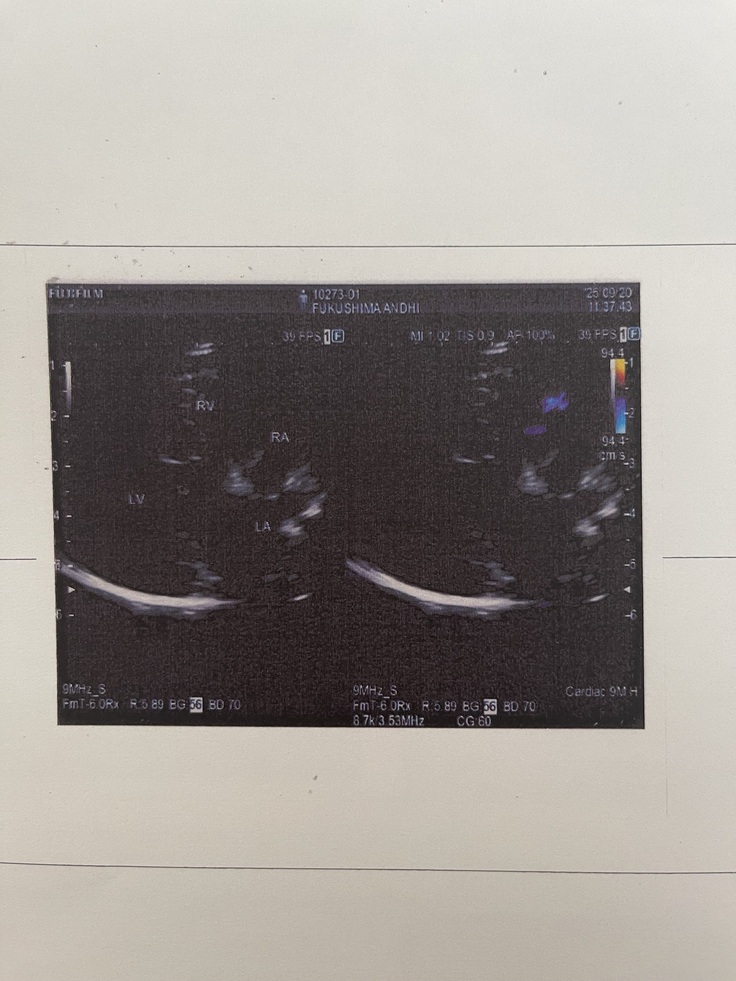

術後6ヶ月検診に行ってきました🏥

9月20日に、

僧帽弁閉鎖不全症手術の術後6ヶ月検診に

行ってきました🚗🐶

結果、今回も問題なく雑音もほぼない状態で

術後の経過は良好とのことでした☺️✨️✨️✨️✨️

次回は来年3月に術後1年検診です🏥